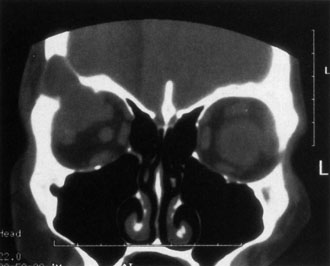

If NFM is suspected, MRI should be ordered of the orbits and brain to exclude noncontiguous intracranial anomalies.93 Magnetic resonance imaging demonstrates the dilated cystic spaces with either a hypointense (lymphatic cyst) or hyperintense (hemorrhagic cyst) signal on T1-weighted images, and a hyperintense signal on T2-weighted images (Fig. 10, A&B).94Layering may be seen within the cysts if there has been a recent hemorrhage leaving unresorbed blood. The CT scans of patients with a deep NFM show low-density, poorly defined masses behind the orbital septum in the extraconal and intraconal spaces, which may indent the globe.3 Calcification within the mass (Fig. 11) and inhomogeneous enhancement of the rim and focal areas within the lesion may be seen that corresponds to abnormal endothelially lined channels.3 Enlargement of the bony orbit can occur, particularly with combined lesions.3,89 If the diagnosis is still unclear, ultrasonography can be performed. A cystic orbital mass is seen on B-scan. A-scan shows features of a solid, cellular tumor: low reflectivity, regular homogeneous internal structure, and marked sound attenuation through the mass.3,89 Standard pulsed Doppler ultrasound confirms no intrinsic flow within the lesions.

Fig. 10. A and B. No flow malformation of the orbit. Sagittal magnetic resonance imaging showing dilated cystic spaces hypointense to muscle on T1-weighted images (A) and hyperintense to muscle on T2-weighted images (B).